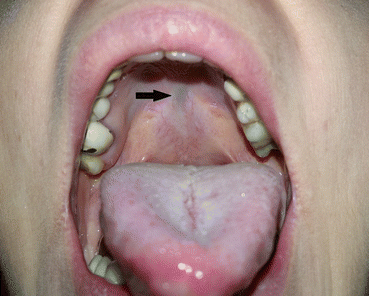

Isolated cleft palate can be unilateral, bilateral, and medial (total or subtotal) (Fig. 7.4a, b) [1, 7, 11]. Pierre Robin sequence includes micrognathia, glossoptosis, and airway obstruction, typically associated with wide U-shaped cleft palate in up to 73–90% of cases (Fig. 7.5) [11, 21]. Patients with submucous cleft palate are in generally asymptomatic, although approximately 15% will develop velopharyngeal insufficiency (VPI) (Fig. 7.6) [1, 6, 11].

Fig. 7.6

Submucosal cleft palate (zona pellucida)